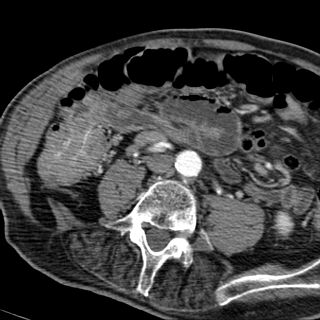

Boudin invagination

ileo-coecale du tumeur villeuse ( fleche rouge

) resoponsable une occlusion . Image TDM en coupe

axiale . |